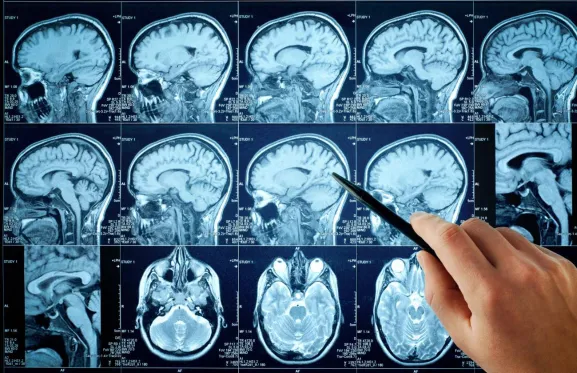

Un equipo científico de las universidades Autónoma de Barcelona (UAB) y de Ruhr en Bochum (Alemania) ha descrito por primera vez las señales electrofisiológicas del cerebro humano asociadas a la memoria y a la extinción de recuerdos de miedo, es decir, al olvido de experiencias negativas o desagradables. La investigación, publicada en Nature Human Behavior, podría servir para diseñar terapias más eficaces en pacientes con estrés postraumático o trastornos de ansiedad.

En el nuevo artículo, los investigadores han descrito las señales electrofisiológicas asociadas al olvido de recuerdos aversivos en humanos. Para ello, han utilizado una técnica reciente llamada análisis de similitud representacional (RSA, por sus siglas en inglés), que permite estudiar cómo las regiones cerebrales representan la información.

Han participado 49 pacientes con epilepsia que ya tenían implantados electrodos en áreas cerebrales relacionadas con los recuerdos de miedo. Durante el experimento, se les mostraron imágenes neutras (como un secador de pelo, un ventilador o una tostadora), algunas de ellas asociadas a un sonido desagradable, mientras se registraba la actividad cerebral. Posteriormente, se repetía el procedimiento sin el estímulo desagradable, con el objetivo de provocar la extinción del recuerdo aversivo.